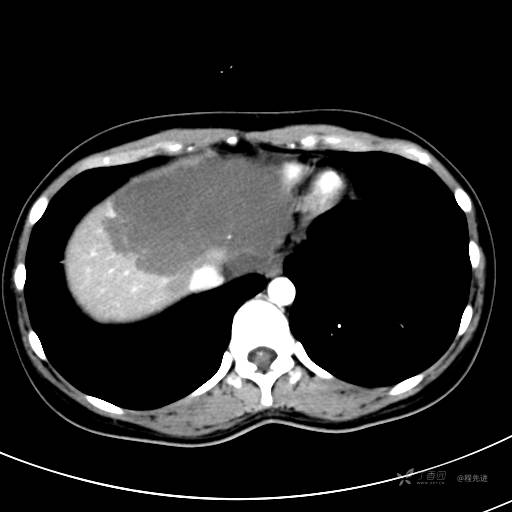

CT平扫+增强,每个序列3张图

CT值 平扫48HU 动脉期66HU 静脉期68HU 延迟期62HU